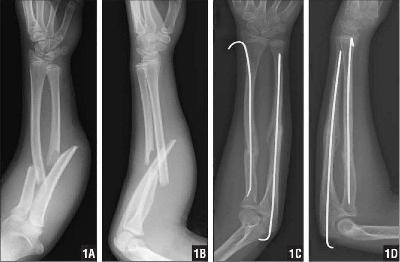

Остеосинтез перелома костей предплечья спицами у ребенка.

Переломы лучевой и локтевой кости в средней трети могут не срастись. Поэтому приходится под ЭОПом провести спицы через дистальный и проксимальный отломки, загнутый кончик погрузить под мягкие ткани, чтобы они не мешали при движениях. После сращения спицы желательно удалить.Ссылка на статьи: Рентген на дому 8 495 22 555 6 8 / Перелом шейки бедра / Рентген на дому в Москве / Компьютерная томография в Москве